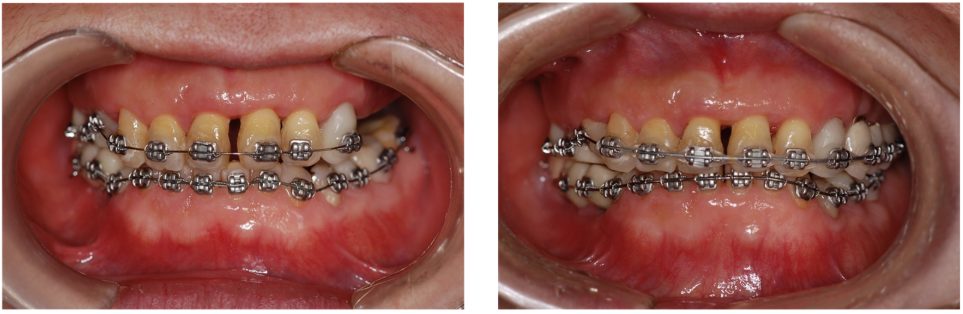

歯周病に罹患した患者さんのインプラント治療の症例②(うえだ歯科)

| 主訴 | 全顎治療希望、全顎的に歯が動く、奥の歯がなくて噛めない。できるだけ綺麗で噛めるようになりたい。 |

| 治療内容 | 全顎的に歯周病、前歯部の被蓋が深く、重度歯列不正が認められるため、 歯周外科を含む歯周治療、矯正治療、インプラント治療、セラミックによる補綴治療後メインテナンスに移行しました。 |

| 治療費 | 5,060,000円(税込)(インプラントすべて含む) |

| 治療期間 | 2年4ヶ月 |

| 治療回数 | 90回 |

| 想定されたリスク | 矯正治療の後戻り、歯周病の再発、食いしばり(パラファンクション)によるセラミックの破折、歯の破折のリスクがありました。 |